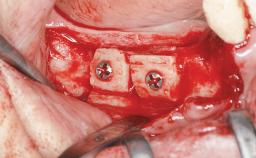

Autologous Iliac-Crest Graft for Anterior Blocks and Bilateral Sinus Floor Elevation in a Completely Edentulous Maxilla

A 56-year-old woman presented for treatment with complete edentulism of the maxilla. She had been using a complete removable denture since she was relatively young (age 30). Her chief complaint at presentation was lack of retention of the upper denture and a desire for a better restoration in order to improve retention, function, and esthetics. An initial clinical examination showed that the anterior maxilla was moderately atrophic both horizontally and vertically, also revealing a vertical deficiency of the posterior alveolar process. The mandible included natural teeth from 45 to 35, with previous extrusion of the anterior teeth that was being orthodontically treated. Also, there were two external hexagon dental implants at sites 46 and 36 that had been inserted elsewhere at a previous point in time. As the conditions in the mandible were healthy, including the teeth and the two implants, the patient had no complaints there.

Bone Augmentation Horizontal|Sinus Floor Elevation|Staged

Augmentation Materials Autogenous chips|Autogenous block(s)

Bone Volume Deficient vertically or deficient vertically AND horizontally